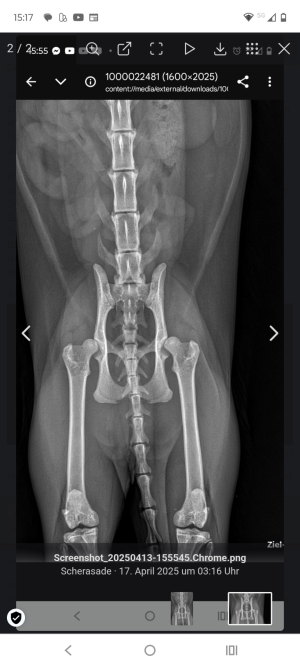

Das ist die Hüfte von Daria rechts schlechter als links. Wird auch als erstes die Seite operiert, hab wegen künstlichen Gelenk nur gutes gehört.

Wird bei ihr auch nicht mehr besser werden. Bekommt jetzt jeden Tag Schmerzmittel. Ist erst 3 Jahre alt und hat noch Muskeln.

Am 13.10 haben wir mit ihr in der Klinik erstmal ein Beratungsgespräch und dann wird überlegt wann und wie alles abläuft. Bin gespannt ob wir mit den 5000€ pro Hüfte richtig liegen.

Fremurskopfrasur kommt für uns nicht infrage. Zu unsicher die Aussichten auf Erfolg und im Alter Ahtrose. Haben unsere Tierärzte gleich abgeraten davon.